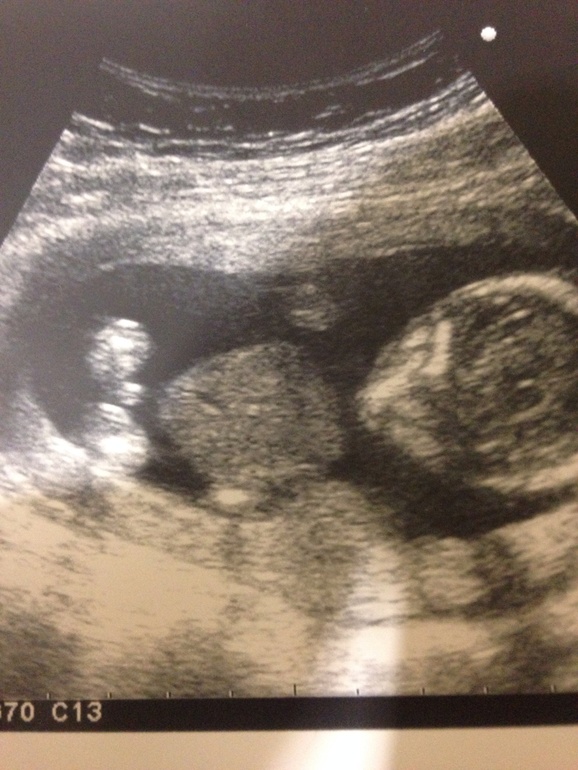

Пол малышаВ общем не вытерпела я и поперлась сегодня на Узи! У нас полных 15 акушерских, по узи отстаем ровно на денечек! Ну не суть! Суть в другом, я шла , чтоб узнать , кто ж в домике живет... В общем всю Б чувствую себя беременной девочкой, а сегодня нам сказали, что скорее всего там парень, и сделали даже фото- доказательство для папы

Но у меня в голове не укладывается,хоть отчасти мне и все равно, ибо Б первая! Но мне кажется, что все таки девочка! Нашла в инете картинку узи с разным полом, и теперь мне еще больше кажется, что девчонка ...

На нижней фотке совсем не тот ракурс для пола, а вот на вашем первом фото либо писюн либо пуповина(обычно на мальчуковых УЗИ хорошо видно и яички и писюн, а на этом фото отросточек который может и пуповиной оказаться :) )

Первое ваше фото это вид снизу и "пока" виден писюн мальчуковый(на УЗИ снизу у девочек две ноги без отросточков), а на примерах вид сбоку. Но на таком сроке еще поменяться может картина

Девочка. Мне один узист врач от бога научил, если отросток к верху — мальчик, к низу девочка.